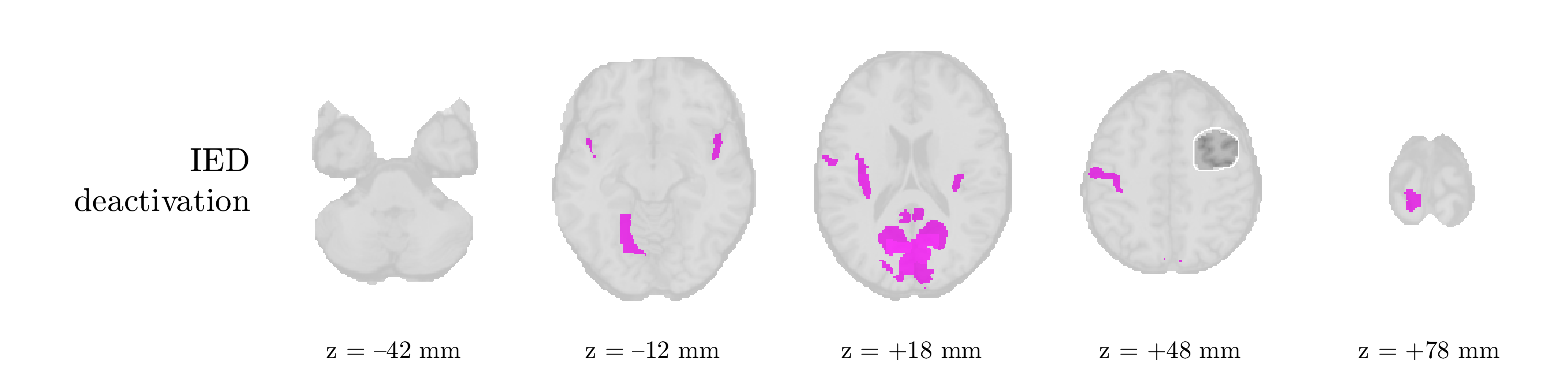

Patient 1

We analyze the solution with sources. Figure 1 shows the EEG signatures and HRF waveforms. One of the sources is highly correlated to the MWF reference (in grey), which was already known from Table B.3. This IED-related source had a typical low-frequency spectrum, which is expected for the typical spike-and-wave interictal discharges. The topography is relatively diffuse, although the highest amplitudes are mostly in the left hemisphere. This is in accordance with the lateralization of ictal onset zone (left temporal lobe, cfr. Table 1). There are some noteworthy observations to be made about some of the other components. The fourth has an unusually sharp spectrum, is mainly localized on two nonadjacent center electrodes, and is sustained for a single period of many seconds Hence, this component likely captured an artifact (of yet unknown origin), although we spotted no large-amplitude changes in the EEG itself. Similarly, the third source is only present at one frontal electrode, and exists in a frequency range above 20 Hz. It might represent a muscle artifact, e.g., due to frowning or twitching of some muscles in the forehead. The HRFs of all ROIs are shown in Figure 1(b). Two of the basis functions seem to have converged to a very similar waveform, which is an unfortunate possibility if two initial HRFs are too close to the same local optimum in their respective parameters. This reduces the expressive power of the basis set, which is clearly visible, since many ROIs have a nearly identical HRF. One of the twenty ROIs with the highest-entropy HRF overlapped the IOZ, although clearly this HRF (bold line) is not among the most dissimilar waveforms for this patient. This is also visible in Figure 2: both the HRF entropy and extremity maps show a small overlap with the delineated IOZ. Despite the good correspondence in the EEG domain, no significant (de)activation of the IED-component is found inside the IOZ.